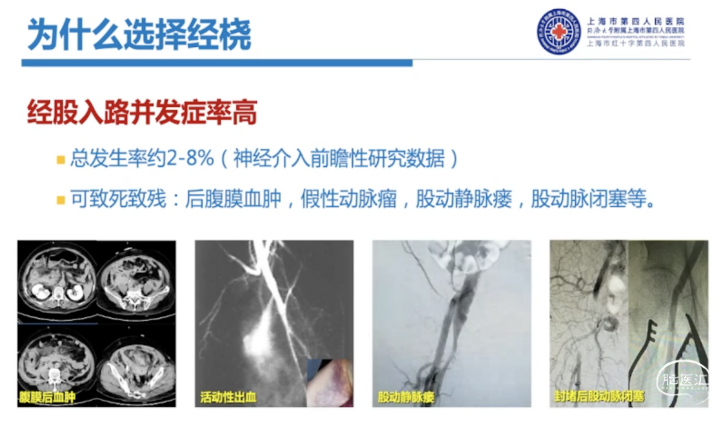

经股入路并发症率高,总发生率约2%-8%(神经介入前瞻性研究数据),且一些严重的股动脉入路并发症甚至可致死致残,如后腹膜血肿、假性动脉瘤、股动静脉瘘、股动脉闭塞等。